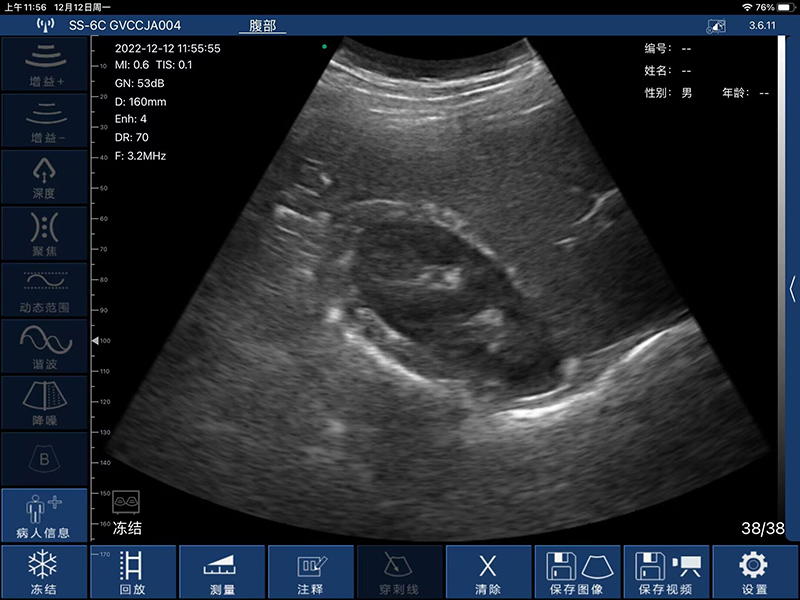

- 扫描深度:90/160/240/305mm,可调

- 显示模式:B、B/M、Color、PW、PDI